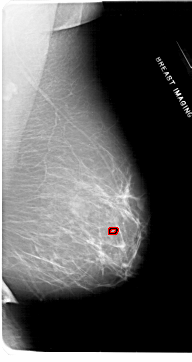

ics_version 1.0 filename A-1953-1 DATE_OF_STUDY 9 6 1992 PATIENT_AGE 50 FILM FILM_TYPE REGULAR DENSITY 2 DATE_DIGITIZED 4 3 1999 DIGITIZER HOWTEK 43.5 SEQUENCE LEFT_CC LINES 6871 PIXELS_PER_LINE 3361 BITS_PER_PIXEL 12 RESOLUTION 43.5 NON_OVERLAY LEFT_MLO LINES 6871 PIXELS_PER_LINE 3526 BITS_PER_PIXEL 12 RESOLUTION 43.5 NON_OVERLAY RIGHT_CC LINES 6616 PIXELS_PER_LINE 3436 BITS_PER_PIXEL 12 RESOLUTION 43.5 OVERLAY RIGHT_MLO LINES 6871 PIXELS_PER_LINE 3631 BITS_PER_PIXEL 12 RESOLUTION 43.5 OVERLAY |

FILE: A_1953_1.RIGHT_MLO.OVERLAY TOTAL_ABNORMALITIES 1 ABNORMALITY 1 LESION_TYPE CALCIFICATION TYPE PLEOMORPHIC DISTRIBUTION CLUSTERED ASSESSMENT 4 SUBTLETY 1 PATHOLOGY BENIGN TOTAL_OUTLINES 1 BOUNDARY |